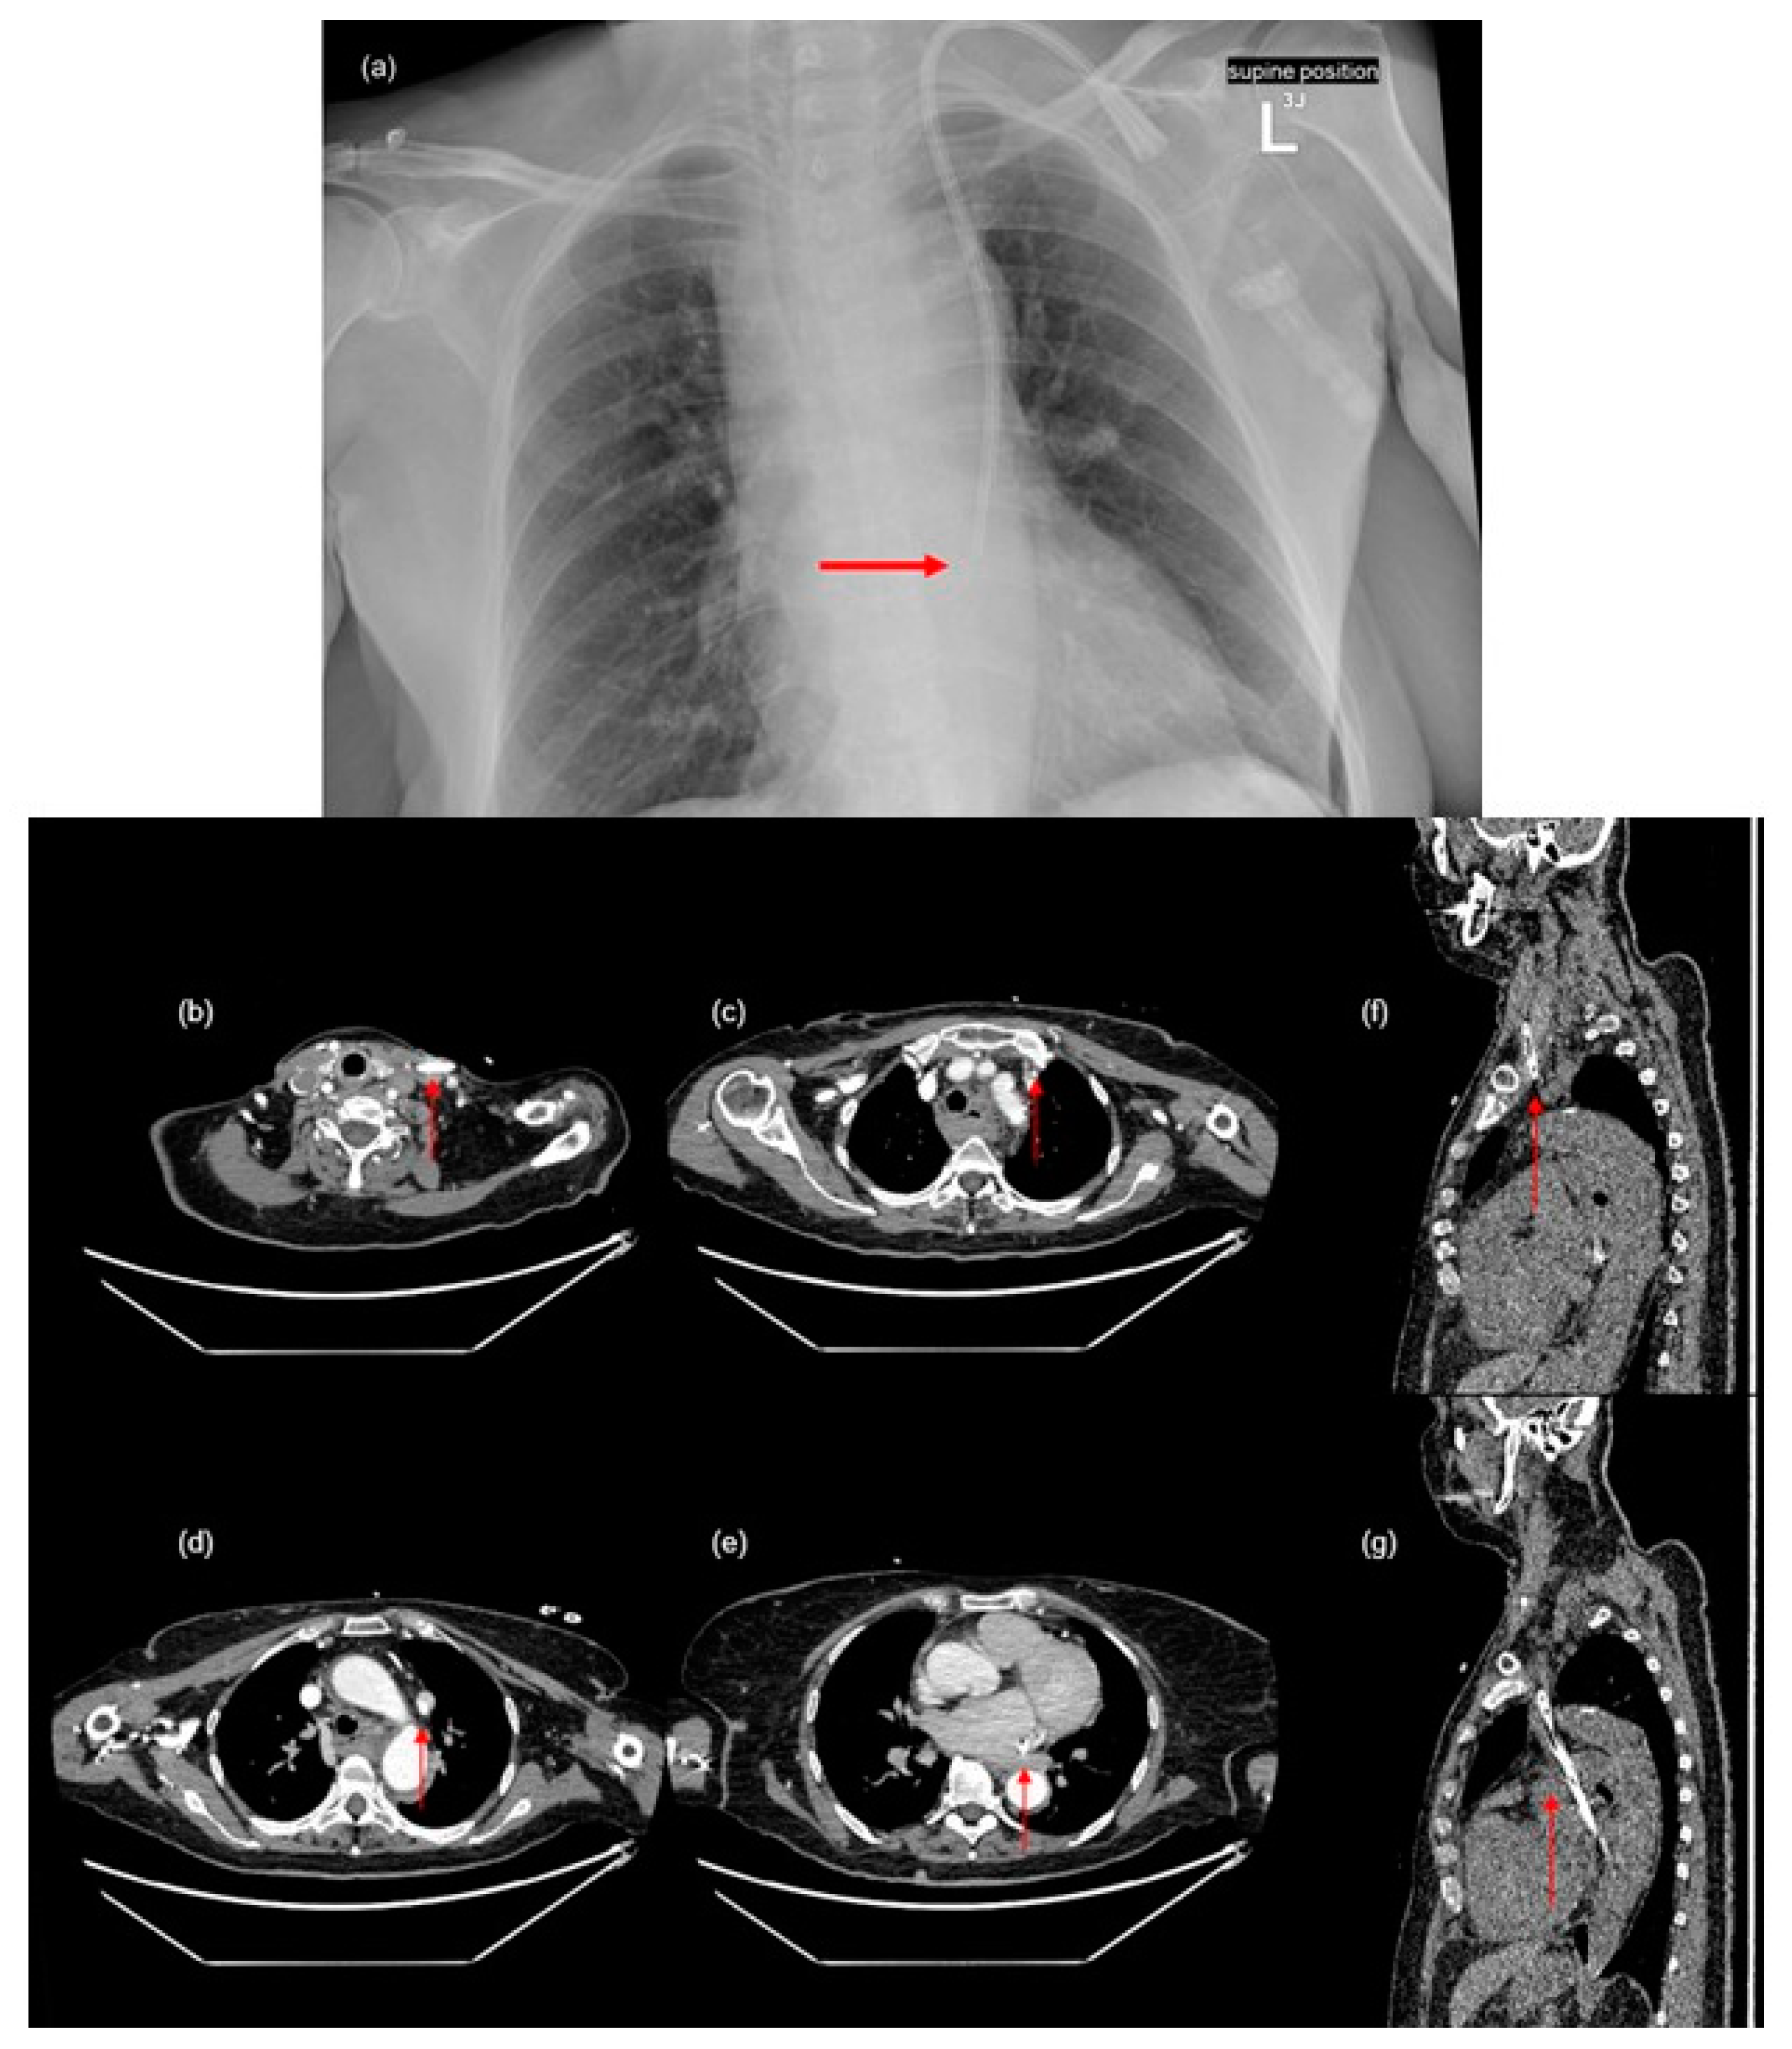

A small pericardial effusion was detected (

Figure 2a). Additionally, the imaging shows a hematoma in the posterior mediastinum and common jugular vein thrombosis (

Figure 2b,c), which are likely complications of the CVC insertion. The size of the hematoma, which was visible from the foramen magnum to the hiatus of the diaphragm, measured at 53 × 28 × 165 mm. Conservative therapy of the mediastinal hematoma was implemented and was effective in this case.

Due to anemia, the patient received two units of red blood cells. Consultations with a cardiologist, cardiac surgeon, and invasive cardiologist led to the recommendation to remove the dialysis catheter inserted in the left jugular vein. Therefore, the permanent hemodialysis catheter was removed, and a temporary CVC was implanted into the left femoral vein. Dialysis was performed on the temporary catheter without complications. Follow-up imaging showed visible regression of the hematoma and no fluid accumulation in the pericardial sac. Additionally, stenosis of the superior mesenteric artery around the head of the pancreas was discovered (

Figure 2d).